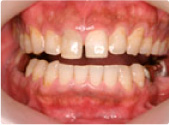

ラミネートベニヤ

治療前

治療後

・特に前歯などで多いが、歯の表面の見える部分だけを削り、 薄いセラミックスを貼り付ける方法です。ちょうど歯の「つけ爪」のようなものです。つけ爪のように何度も変えたりするわけではありません。

・変色がひどい場合や、歯の形を変えたりする場合に用いらる方法です。

この患者さんは前歯6本のみ行いました。下の歯と比べても違いはよく分かっていただけるかと思います。

著しい歯の変色や形の悪さでお悩みの方には、この方法できれいな歯に見せることができます。